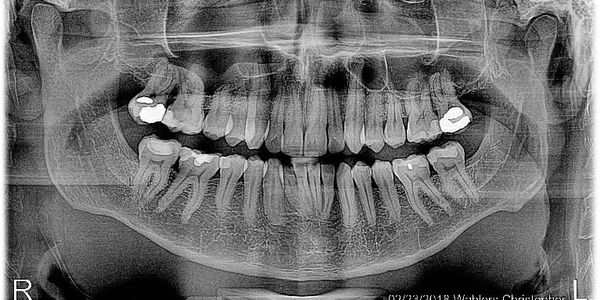

A panoramic x-ray is a specialized dental imaging technique that captures your entire mouth — teeth, jaws, and surrounding structures — in a single, wide-view image. Unlike standard bitewing or periapical x-rays that focus on small areas, panoramic x-rays provide a comprehensive overview, helping your dentist assess overall oral health and detect issues that might not be visible in traditional x-rays.

Panoramic x-rays are commonly used to:

• Full-mouth view in a single image: Offers a complete picture of your oral structures without taking multiple small x-rays.

• Non-invasive and quick: The process is comfortable, with minimal patient effort. The machine rotates around your head, capturing the image in seconds.

• Lower radiation exposure: While panoramic x-rays cover a larger area, modern digital systems keep radiation low.

• Helps in early detection: Provides valuable insights into hidden dental issues, allowing for early intervention and more effective treatment planning.